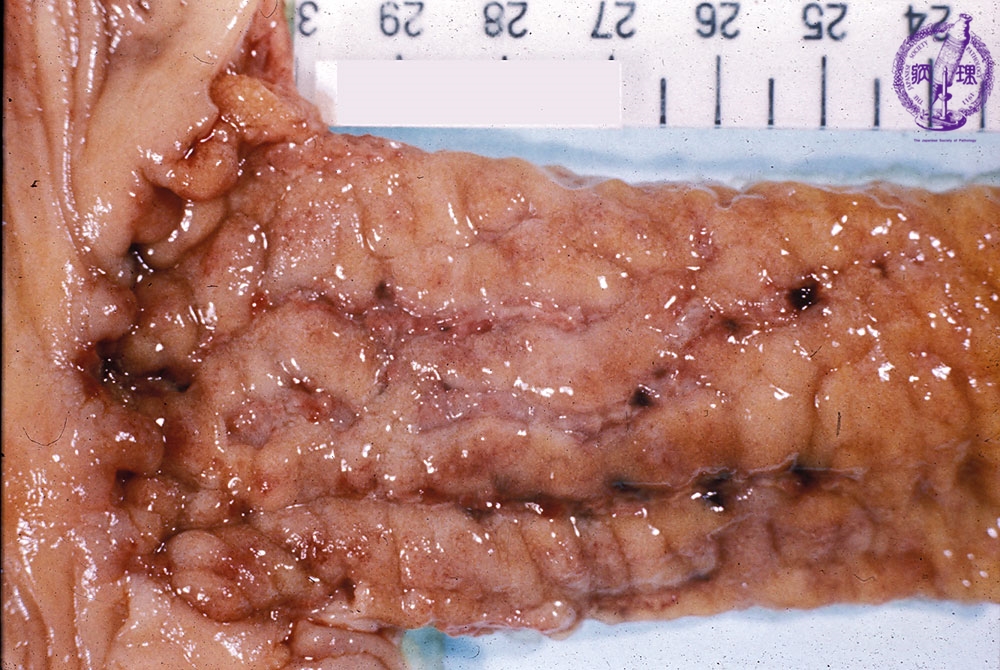

- ★(3)Crohn’s disease

Gross appearance: Linear ulcers (blue) and a cobblestone appearance (yellow) are distinctly seen.